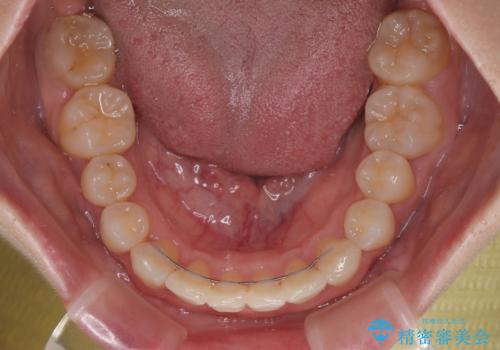

右上と左下の第一大臼歯2本が周辺の歯と比べて位置がずれていたため、ゴムかけやワイヤーに曲げを入れることで移動を試みましたが、どうよら癒着をしており、移動困難と判断されました。

見た目や咬み合わせに違和感がないとのことで、癒着歯の無理な移動は試みずに治療を終えることとしました。